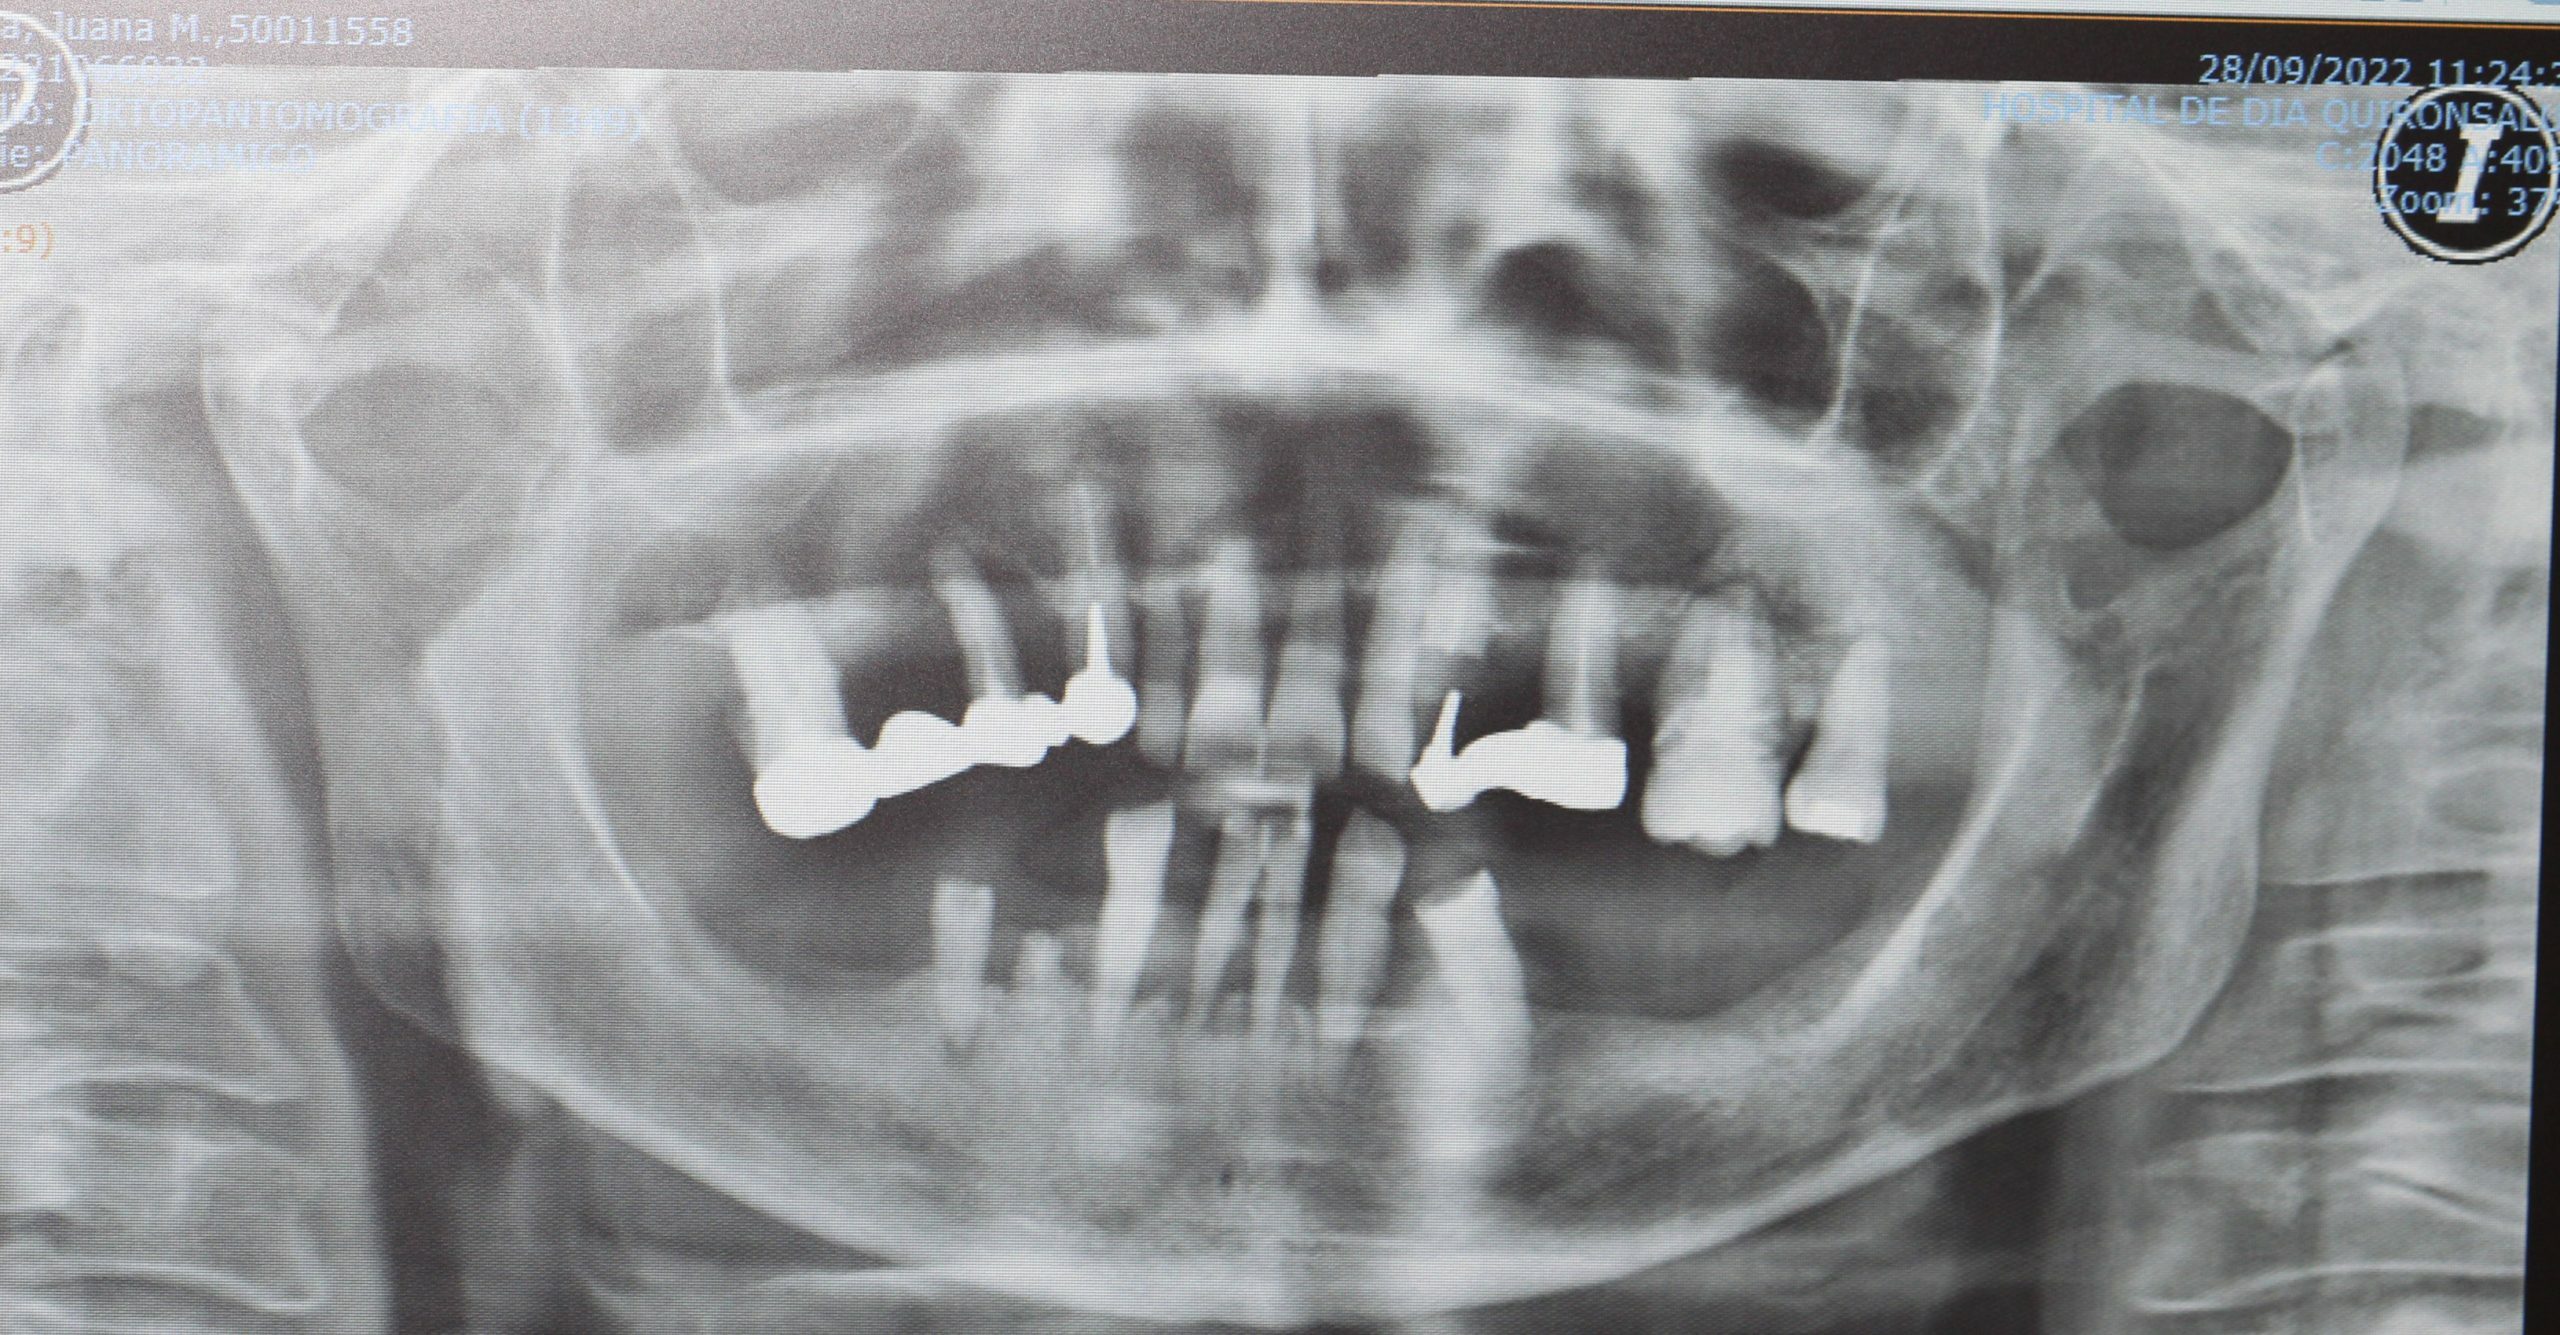

El éxito de la implantología depende de la existencia de hueso adecuado para soportar el implante. La pérdida dental a menudo causa reabsorción ósea. Diagnosticamos Defectos Óseos Parciales o Afecciones Avanzadas y Crónicas que requieren reconstrucción ósea generalizada. La planificación virtual es indispensable.

Casos de Éxito: Experiencia que Genera Confianza

Nuestra experiencia se centra en la implantología compleja y la regeneración ósea, logrando rehabilitaciones dentales estables y duraderas con el máximo rigor médico.